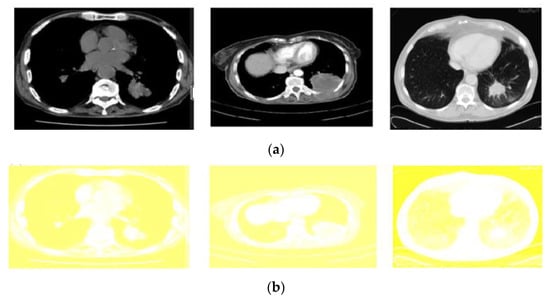

All the images used in this research are also accessible in the database, with the pivotal point of view. Here, the framework size is (256 × 256) or (512 × 512) and 16 bits for every pixel. Lung Image Database Consortium (LIDC) is where the JPEG format of lung images is available. For research purposes of radiologists, they can easily access that database through Cancer Imaging Archive (CIA) [29]. Some samples from the databases are shown in Figure 3. The proposed system data set consists of images of 290 patients, of which 250 patient datasets are used for training the classifier, and the remaining 40 patient datasets are used for validation. The data set obtained is of DICOM format and is converted to 512 × 512 by pre-processing method without data loss for further partitioning and refinement purposes. Table 1 summarizes the dataset used, and Table 2 shows the scanner difference.

Figure 3.

CT image of lungs from the dataset: LIDC in the different sagittal planes.